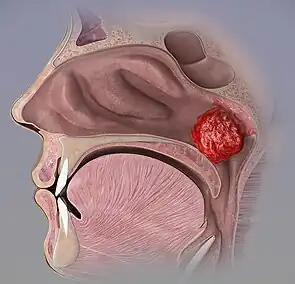

| Adenoid hilighted in green. | |

Adenoid hypertrophy (enlarged adenoids) is the unusual growth (hypertrophy) of the adenoid (pharyngeal tonsil) first described in 1868 by the Danish physician Wilhelm Meyer (1824–1895) in Copenhagen. He described a long term adenoid hypertrophy that will cause an obstruction of the nasal airways. These will lead to a dentofacial growth anomaly that was defined as "adenoid facies" (see long face syndrome).

Enlarged adenoids can become nearly the size of a ping pong ball and completely block airflow through the nasal passages. Even if enlarged adenoids are not substantial enough to physically block the back of the nose, they can obstruct airflow enough so that nasal breathing requires an uncomfortable amount of work, and inhalation occurs instead through mouth breathing. Adenoids can also obstruct the nasal airway enough to affect the voice without actually stopping nasal airflow altogether.[1]

Nasal blockage is determined by at least two factors: 1) the size of the adenoids, and 2) the size of the nasal pharynx passageway. The adenoid usually reaches its greatest size by about age 5 years or so, and then fades away ("atrophies") by late childhood - generally by the age of 7 years. The lymphoid tissue remains under the mucosa of the nasopharynx, and could be seen under a microscope if the area was biopsied, but the mass is so reduced in size that the roof of the nasopharynx becomes flat rather than mounded. Just as the size of the adenoids is variable between individuals, so is the age at which adenoids atrophy.